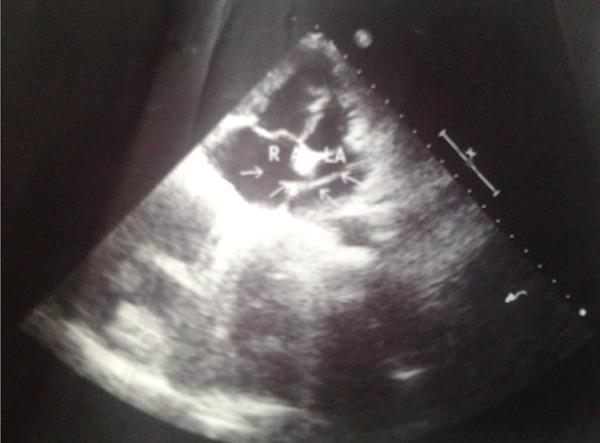

Percutaneous pulmonary balloon valvuloplasty as a procedure of choice in adults has been established since the last three decades. Even though the complications are rare, they are scarcely reported in the literature. We report such a case in an adult female patient of severe pulmonary valular stenosis in whom, entrapped catheter across the fossa ovalis was noted in chest x-ray and echocardiogram following unsuccessful percutaneous pulmonary balloon valvuloplasty. Our case emphasizes this rare complication and its successful surgical outcome.